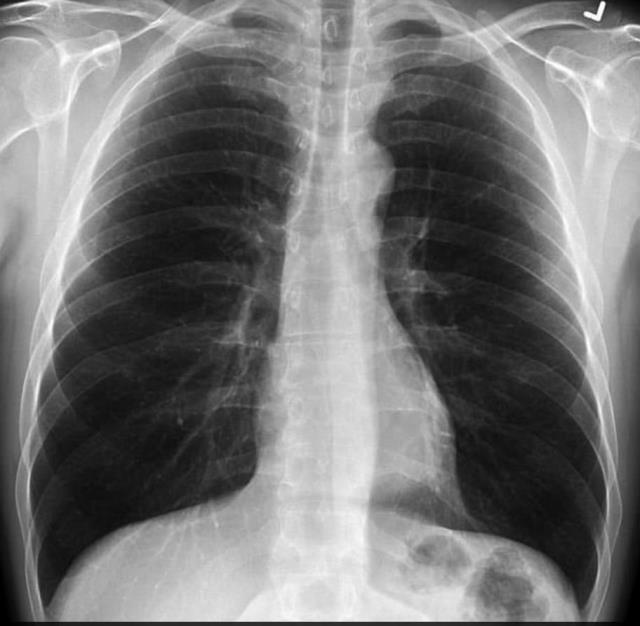

Bankhead-Kendall, kıyaslama yapmak için sağlıklı bir bireyin akciğer filmini de paylaştı.

Bankhead-Kendall, kıyaslama yapmak için sağlıklı bir bireyin akciğer filmini de paylaştı."NEFESLERİ KESİLİYOR HATTA BAYILIYORLAR"